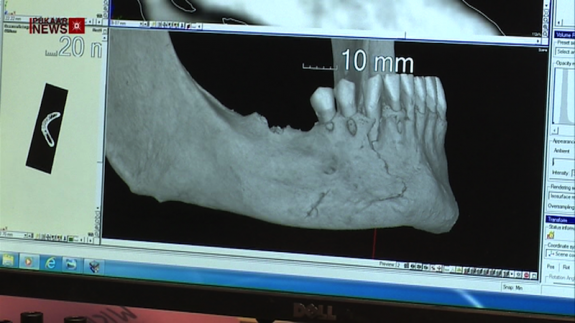

The University of Leicester have revealed the injuries inflicted on King Richard III during the Battle of Bosworth in 1485 thanks to new research. …